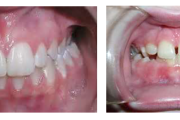

Turritavad ülemised lõikehambad.

Ülemise hambakaare kitsenemine ehk tagumiste hammaste risthambumus.